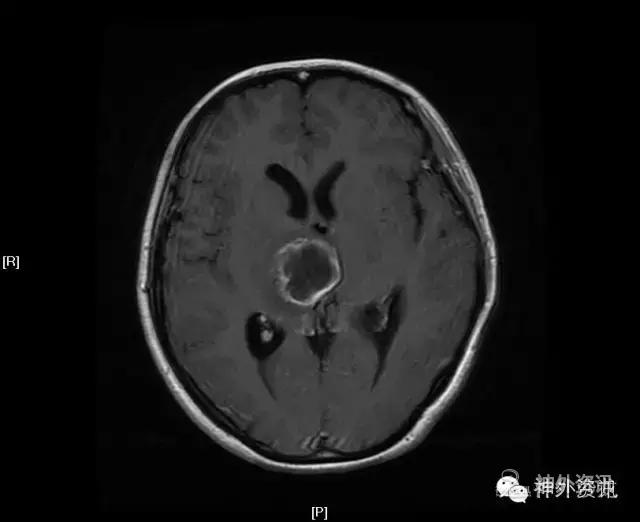

MRI:右侧丘脑占位,考虑胶质瘤可能性大(Ⅲ-Ⅳ级),病灶累及中脑右侧大脑脚,轻度脑积水;不除外转移瘤可能,请结合相关病史及检查。

影像学检查: